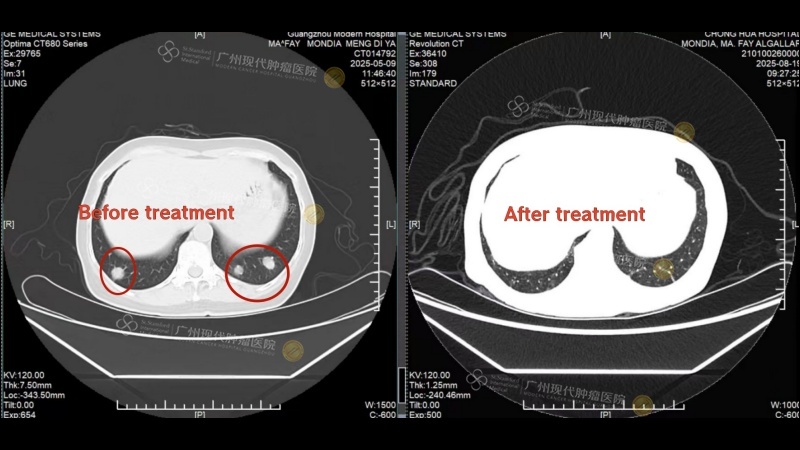

Comparison of lung metastases before and after treatment

After completing the 2nd treatment session, a follow-up CT scan at her local hospital revealed significant shrinkage of the breast tumor and the disappearance of most lung metastases. These remarkable results rekindled her hope—what she once believed was an insurmountable battle now seemed winnable at Modern Cancer Hospital Guangzhou.